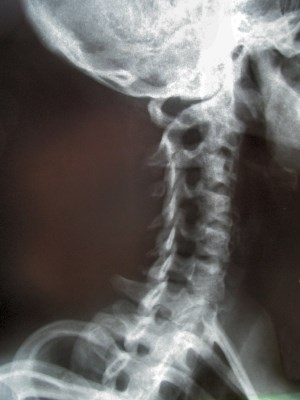

NACKSKADAD

Skada i nacken genom whiplashtrauma eller på annat sätt kan ge livslånga problem med smärta i botten. Förutom smärtan möter den skadade olika symtom och symtomen kan också variera över tid. Exempel på vanliga problem är obalanser, yrsel, koncentrationssvårigheter, domningar i armarna, problem med käkarna, synen mm mm listan kan göras oändlig